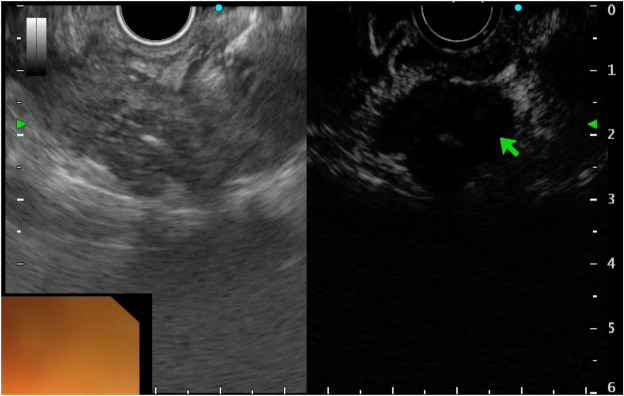

VÍDEO: Contrast-enhanced harmonic EUS–guided radiofrequency ablation of hepatocellular carcinoma: a new horizon in endohepatology

junho 23, 2024junho 26, 2024SOBED-RJ